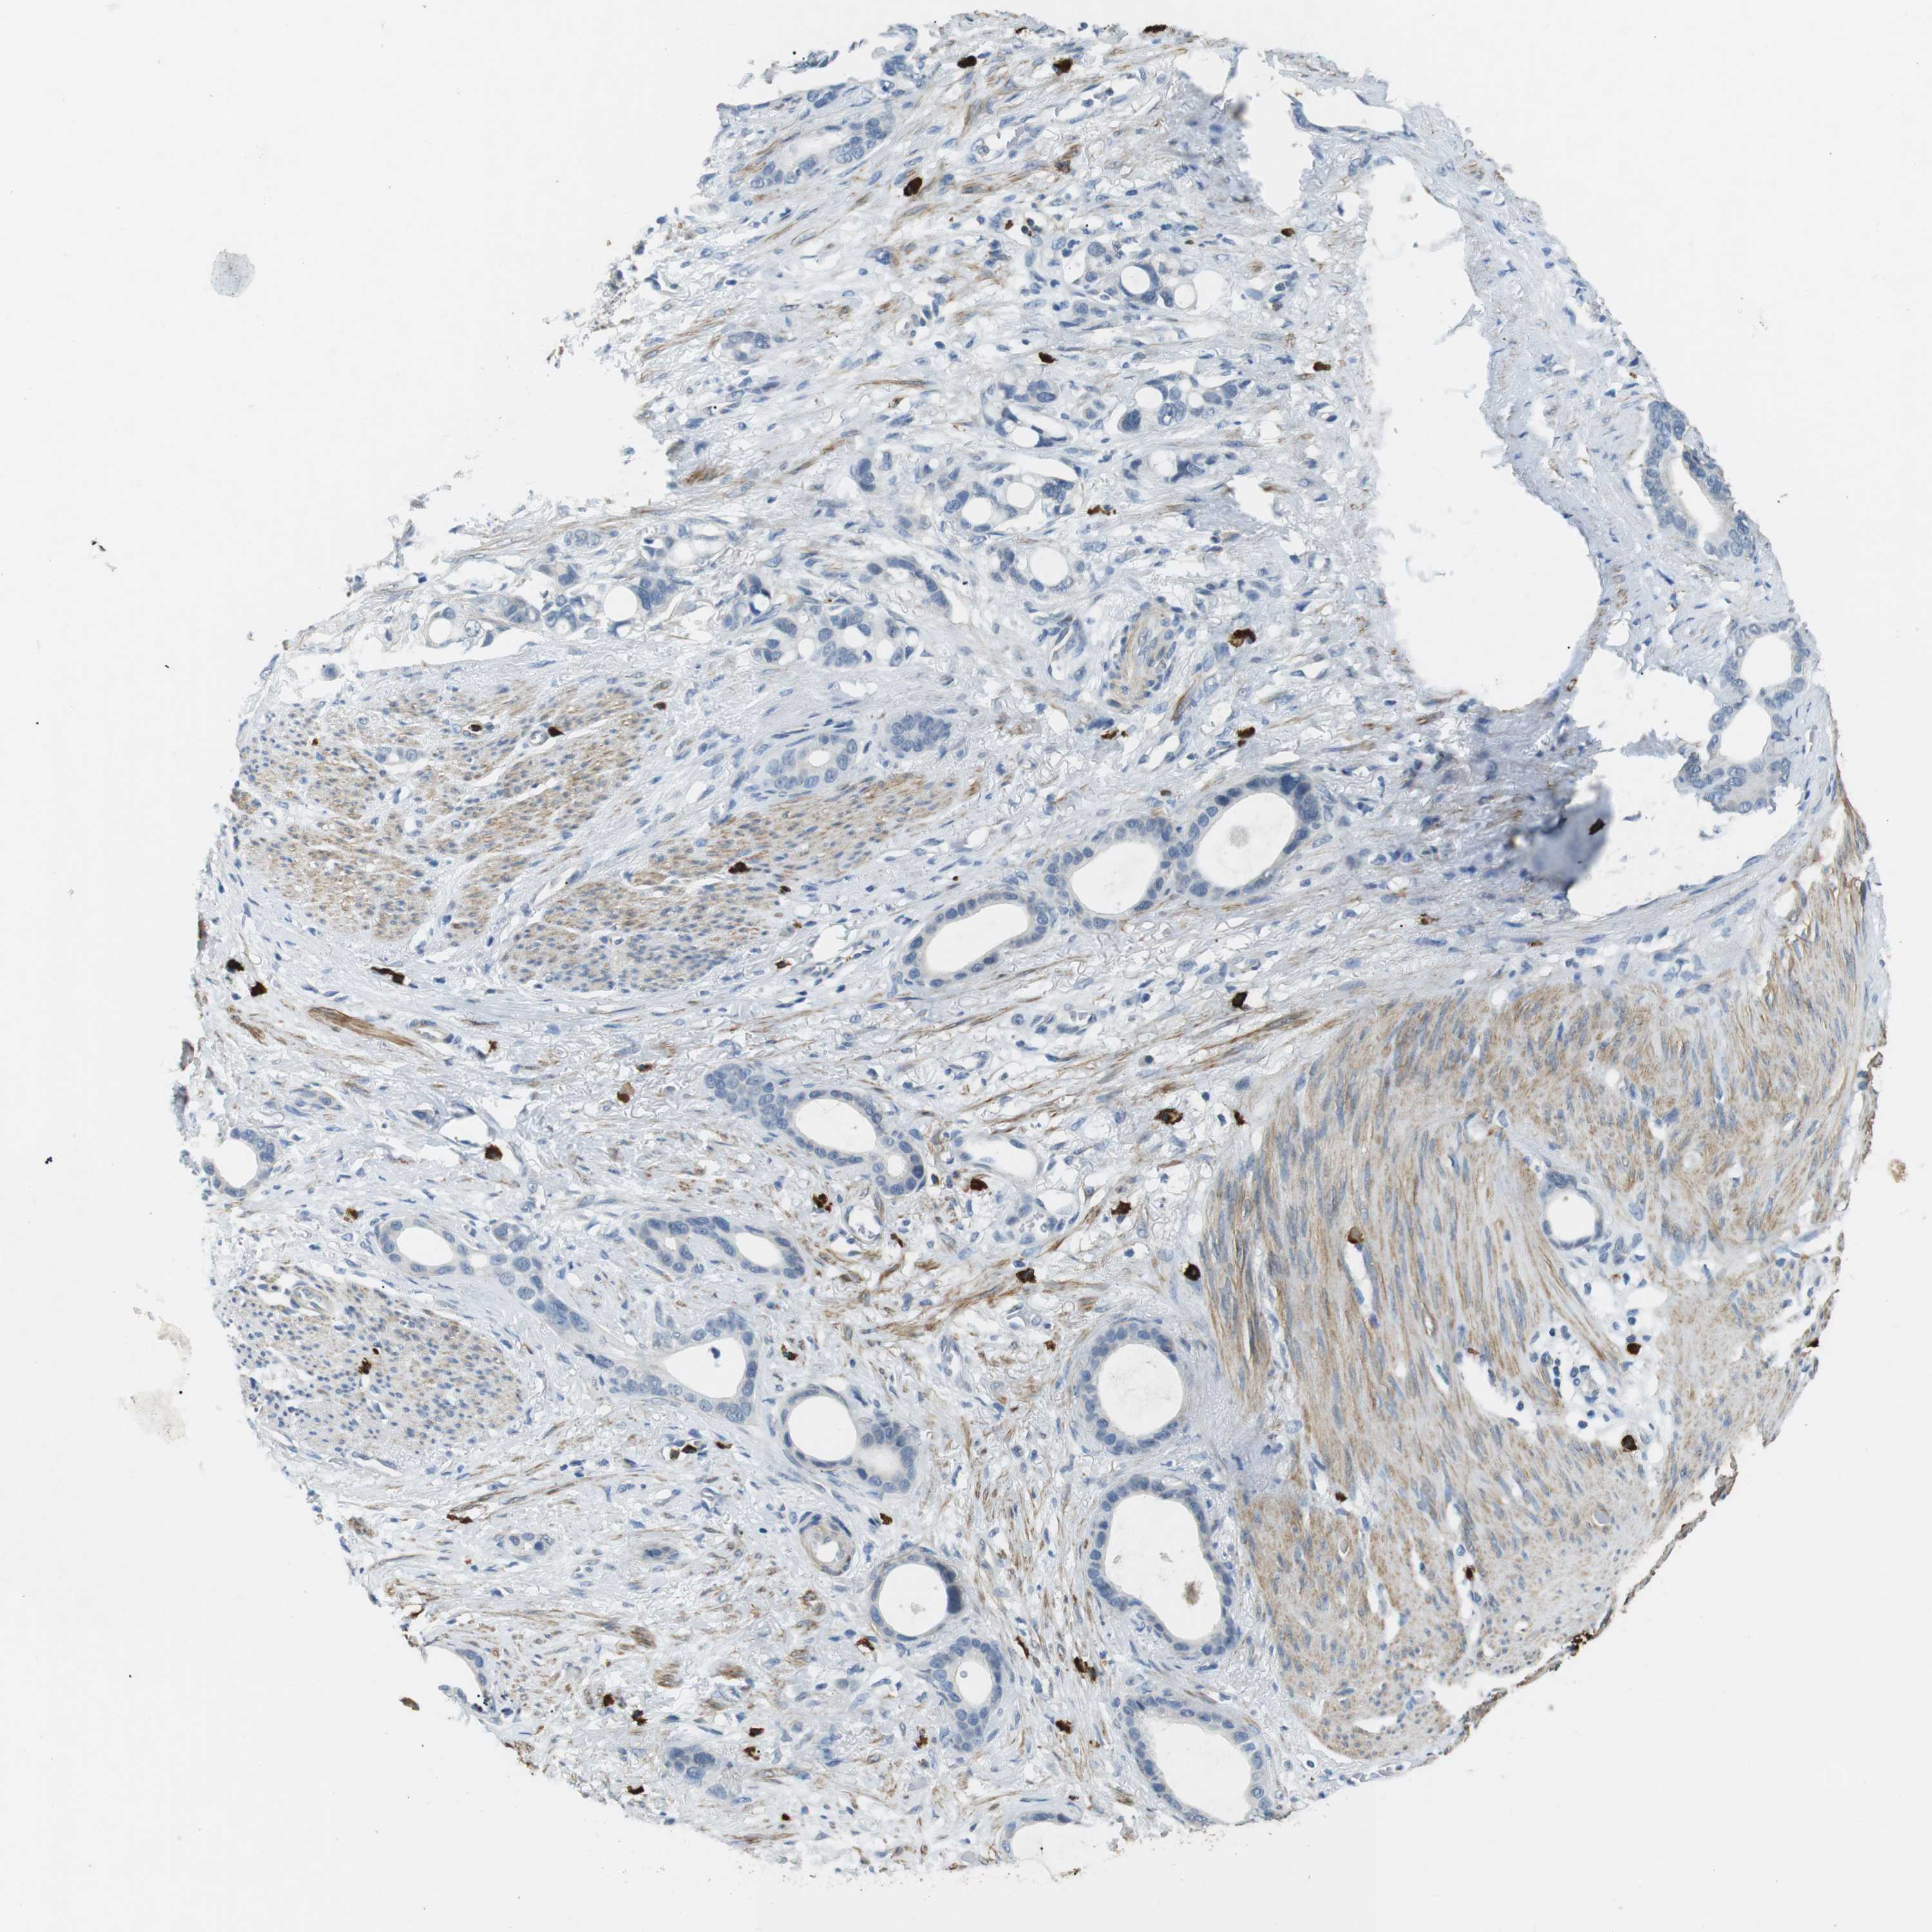

STOMACH CANCER - Protein expressioni

A mouse-over function shows sample information and annotation data. Click on an image to view it in a full screen mode. Samples can be filtered based on level of antibody staining by selecting one or several of the following categories: high, medium, low and not detected. The assay and annotation is described here.

Antibody stainingi

Antibody staining in the annotated cell types in the current human tissue is reported as not detected, low, medium, or high, based on conventional immunohistochemistry profiling in selected tissues. This score is based on the combination of the staining intensity and fraction of stained cells.

Each image is clickable and will lead to virtual microscopy that enables deeper exploration of all samples and also displays staining intensity scores, fraction scores and subcellular localization as well as patient and tissue information for each sample.

Antibody HPA015624

Staining

High

Medium

Low

Not detected

Intensity

Strong

Moderate

Weak

Negative

Quantity

>75%

75%-25%

<25%

None

Location

Nuclear

Cytoplasmic/membranous

Cytoplasmic/membranous,nuclear

Adenocarcinoma, NOS

Adenocarcinoma, High grade